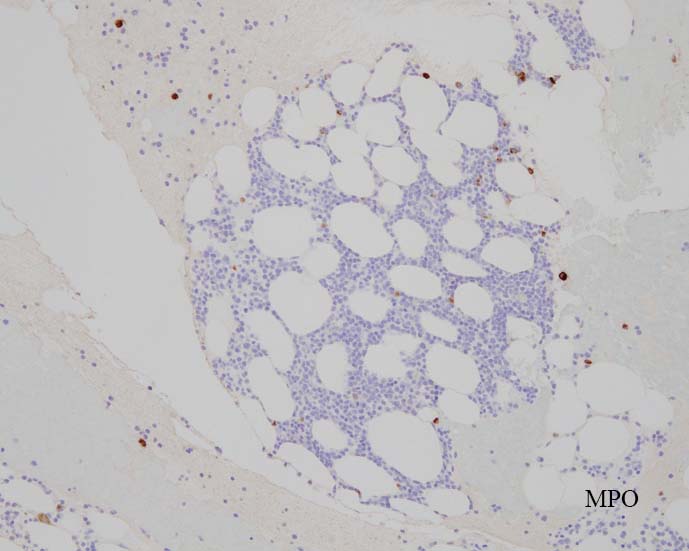

免疫染色

blastic cellsは, CD45+, CD34+, CD38+, TdT+, CD7+, HLA-DR+, CD123+. cCD3-, sCD3-(FCM), CD20-, CD19-とCD79a-(?) (plasma cellが陽性でIHCでは判定が難しい), MPO-.

CD3-, CD79aは増加しているplasma cellsが陽性で判定が難しい. CD10-, MPO-. (CD10は画像欠)